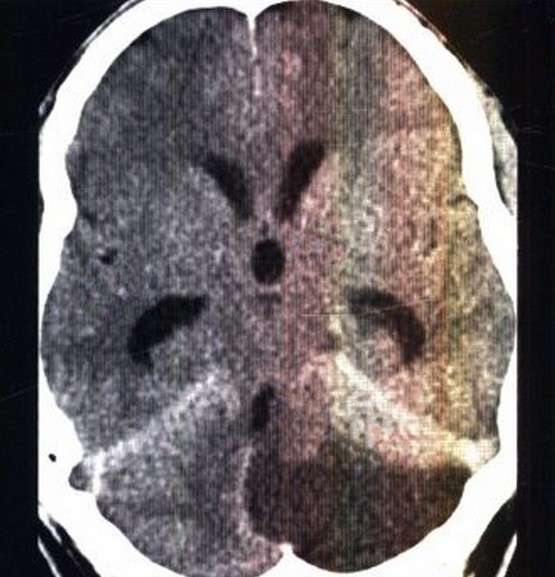

Внутричерепная гипотензия: КТ-исследования и их интерпретация